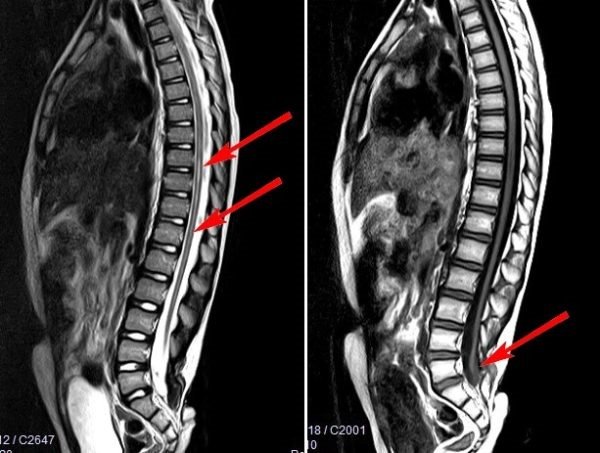

- МРТ – единственная методика, позволяющая максимально точно определить, насколько поврежден спинной мозг, выявить локализацию фиксации и другие нарушения.

МРТ снимок позволяет быстро выявить патологический процесс

«Золотым стандартом» диагностики позвоночника и спинного мозга является магнитно – резонансная томография (МРТ), позволяющая определить анатомо–морфологические взаимоотношения в сложной анатомической системе «спинной мозг — позвоночный канал — мягкие ткани, выявить скрытые формы спинальных пороков и уточнить прямые и косвенные признаки «фиксации спинного мозга». Патогномоничный симптом синдрома фиксированного спинного мозга — опущение конуса спинного мозга ниже L1 – L2 позвонка, с признаками утолщения конечной нити.